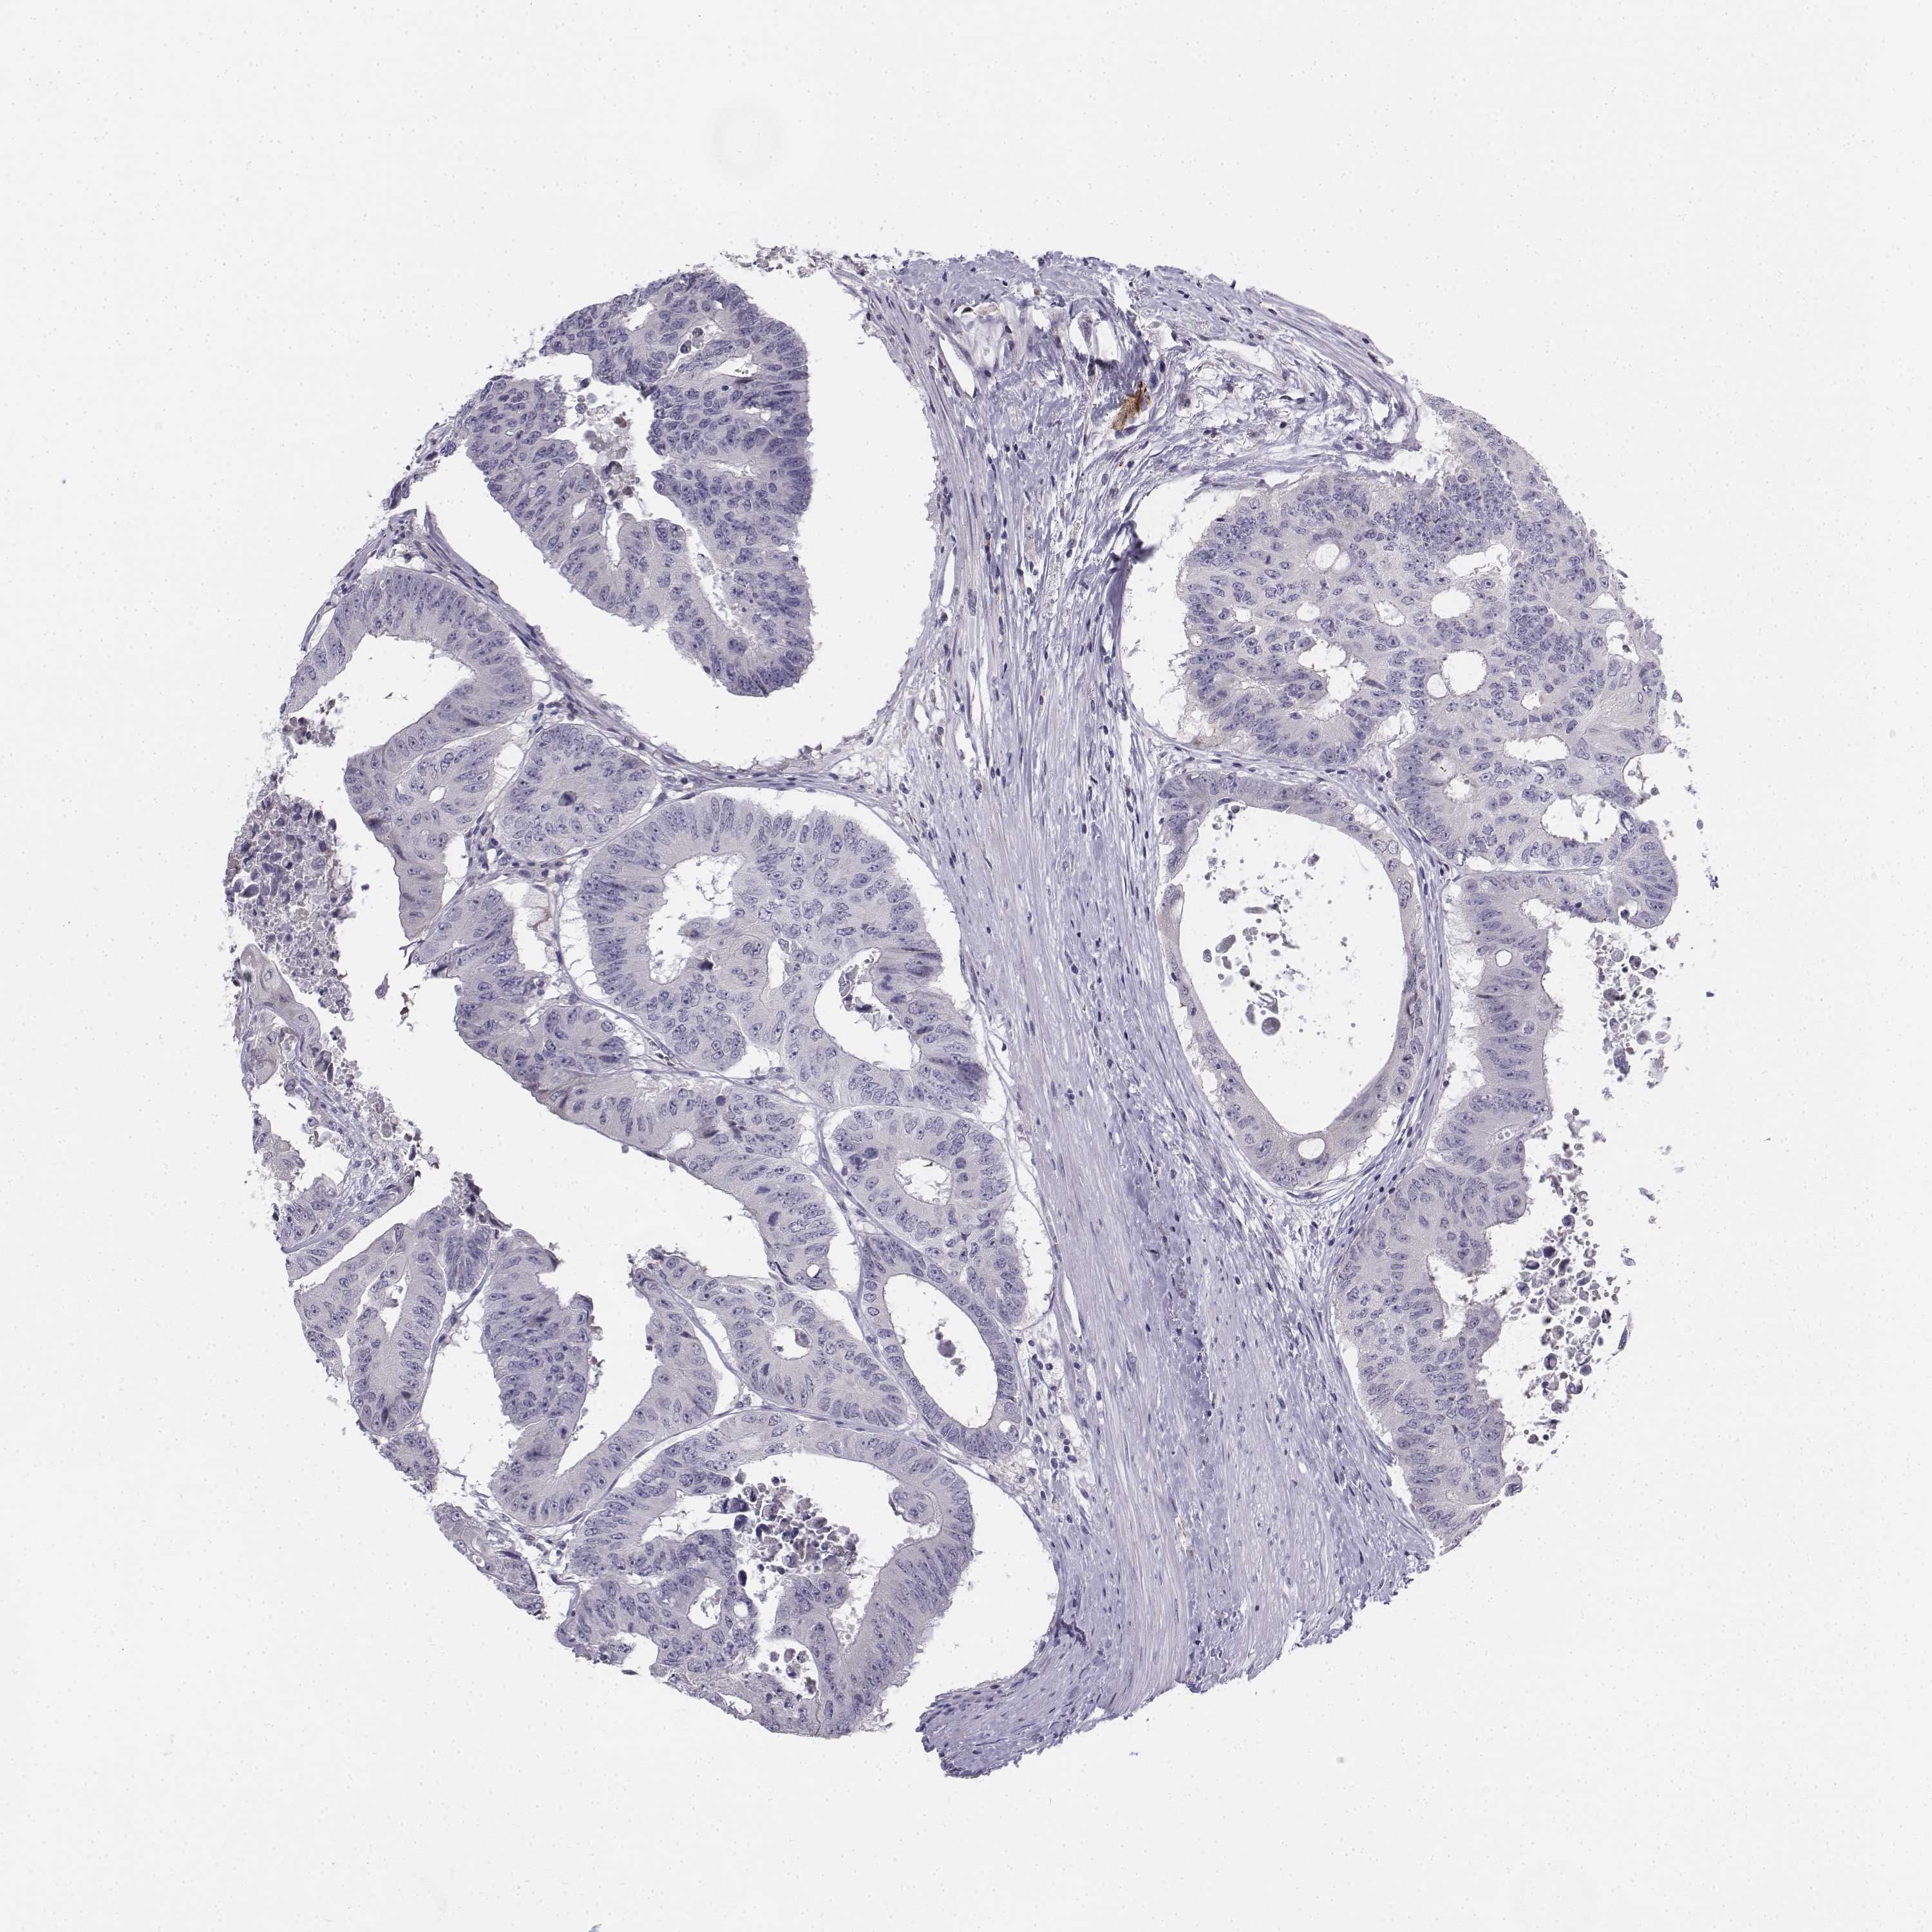

CANCER COLORECTAL CANCER Show tissue menu

Colorectal cancer

Human cancer

Colon adenocarcinoma